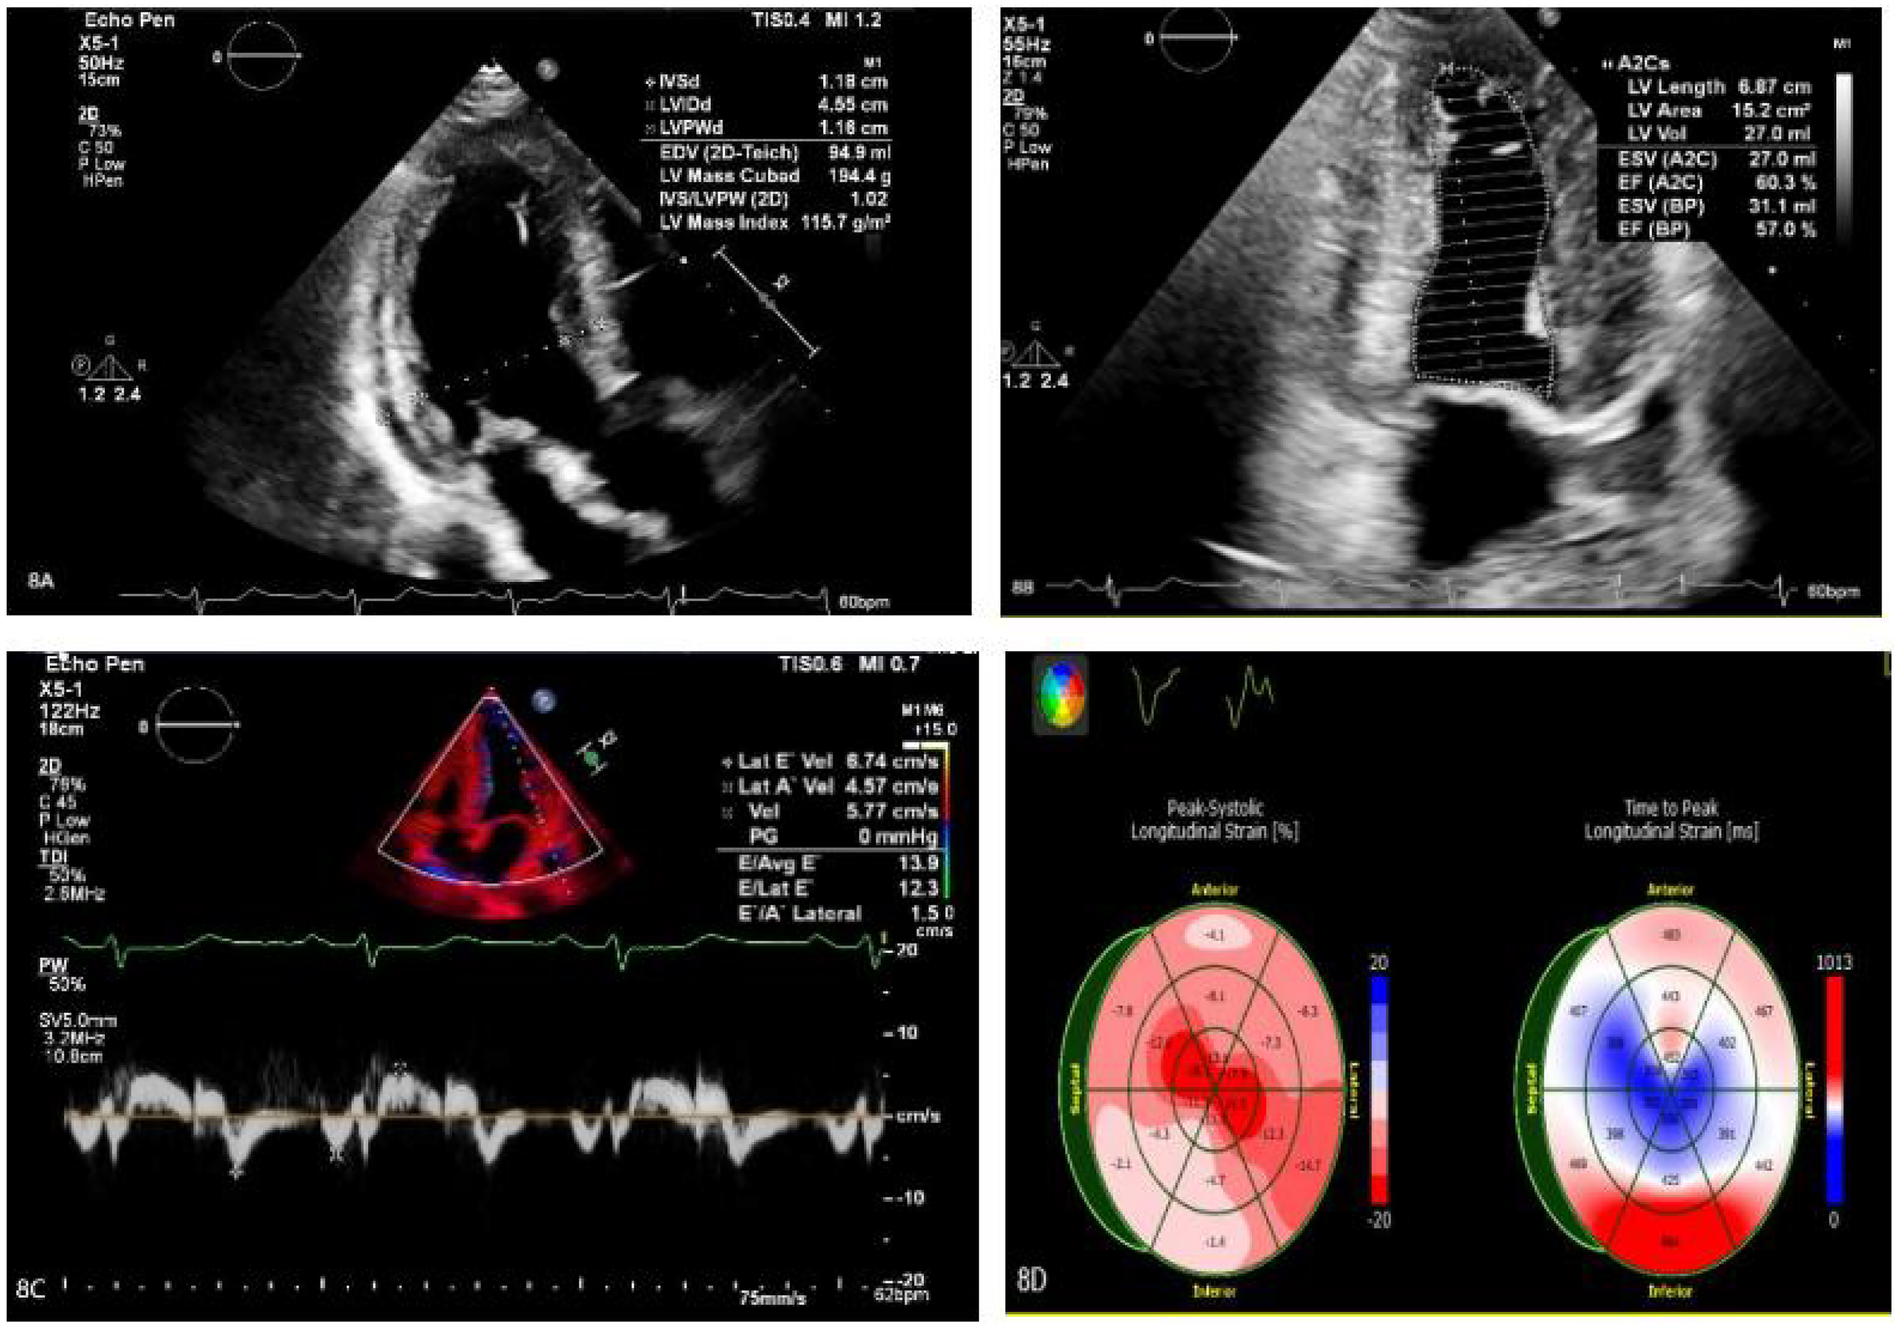

Treatment for the patient began on two weeks later. The first course of treatment using the VSD regimen (bortezomib 2.3 mg + cyclophosphamide 1.2 g + dexamethasone 40 mg) showed poor efficacy. The treatment was then changed to the DVCD regimen (bortezomib 2.3 mg + daratumumab 800 mg + cyclophosphamide 0.5 g + dexamethasone 40 mg). Due to persistently high heart rate after chemotherapy, the patient exhibited atrial flutter and paroxysmal atrial fibrillation on ECG, with a programmed AT/AF burden of 4%. Following chemotherapy, the patient developed persistent tachycardia accompanied by atrial flutter and paroxysmal atrial fibrillation. Despite receiving standard anticoagulation, electrical cardioversion, and diuretic therapy, serial follow-up visits revealed persistently elevated BNP levels. These findings suggested the possible presence of occult arrhythmias that had not been adequately captured or assessed by conventional electrocardiographic monitoring.Given the diagnosis of systemic AL-CA—a condition known to predispose the cardiac conduction system to infiltration by amyloid deposits—the patient was at significantly increased risk for developing advanced atrioventricular block, prolonged asystolic pauses, and even sudden cardiac death. However, at that time, there were no clear indications warranting immediate implantation of a permanent pacemaker or an implantable cardioverter-defibrillator (ICD). Therefore, to establish a definitive causal relationship between the patient's symptoms and potential arrhythmic events, and to enable precise risk stratification without premature device intervention, the clinical team decided to implement long-term, continuous outpatient cardiac rhythm monitoring. Accordingly, an implantable cardiac monitor (ICM) was implanted two months after the initiation of systemic therapy to objectively detect and evaluate potentially life-threatening bradyarrhythmias or tachyarrhythmias. One year later, the patient received HD-Mel conditioning (melphalan 150 mg on day 1, 100 mg on day 2, with supportive liver and stomach protection, antiemetic, prophylactic antimicrobial, and antithrombotic therapies) followed by autologous peripheral blood hematopoietic stem cell transplantation. Maintenance therapy with daratumumab was continued post-transplant. Subsequently, the patient's dFLC levels were normalized (1.35 mg/L) and stabilized. Echocardiography showed that the ventricular muscle had become thinner compared to before (LVPWd 1.16 cm, right ventricular free wall 0.45 cm), with left ventricular systolic function within the normal range (EF: 57%) and mildly reduced left ventricular diastolic function (grade 1), LV GLS = −10.4% (Figure 8). This year, the patient presented again with “dizziness and chest tightness for one week, accompanied by two episodes of syncope.” ICM interrogation revealed paroxysmal atrial fibrillation with a 7-s pause (Figure 9), prompting implantation of a permanent pacemaker (Figure 10). Since implantation of the dual-chamber pacemaker, the patient has not experienced any further episodes of syncope, and exercise tolerance during daily activities has significantly improved. We programmed the pacing rate at 80 beats per min. As of the time of manuscript submission, the patient had no recurrence of atrial fibrillation–related symptoms, and ambulatory electrocardiographic monitoring showed no frequent or rapid atrial arrhythmias.

Figure 8

(A–C) The ventricular myocardium appears thinner compared to previous measurements: left ventricular posterior wall thickness (LVPWd): 1.16 cm; right ventricular free wall thickness: 0.45 cm. Left ventricular systolic function is normal (EF: 57%), with mildly reduced left ventricular diastolic function (Grade 1). (D) The left ventricular global longitudinal strain (LV GLS) is −10.4%. Apical strain is preserved, while basal and mid-segment strains are reduced.